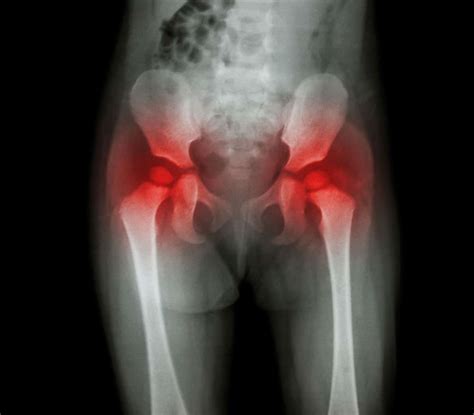

Managing Pain and Inflammation

Pain management is essential not only for comfort but also for ensuring you can participate in physical therapy effectively. If pain is uncontrolled, it becomes difficult to move, which in turn leads to stiffness and a slower recovery. A balanced approach is usually recommended, combining medication with non-pharmacological methods.